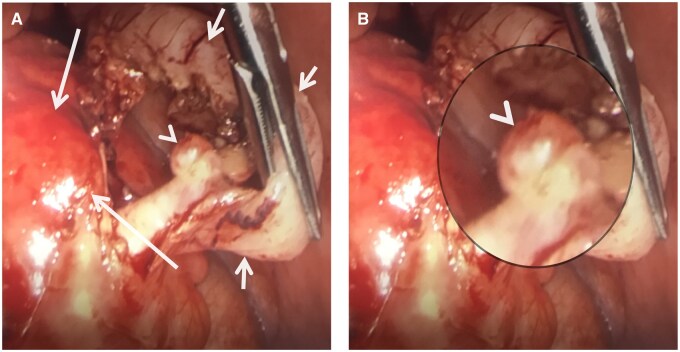

阑尾憩室炎,虽然罕见,是一个重要的鉴别诊断的情况下,右髂窝疼痛。以前,由于其临床表现相似,常被认为是急性阑尾炎的一种变体。然而,最近的研究表明,阑尾憩室炎是一个独特的临床实体,具有不同于急性阑尾炎的人口学特征和临床特征。它还与严重发病和死亡的高风险相关,需要及时诊断和管理。在此报告中,我们报告了一例58岁男性蚓状阑尾憩室炎患者,并回顾了相关文献。我们描述的分类阑尾憩室病和憩室炎,他们的临床表现,和他们的潜在并发症。我们概述了阑尾憩室炎和急性阑尾炎的影像学表现,并讨论了诊断成像在区分这两种疾病中的重要作用。

Appendiceal diverticulitis, although rare, is an important differential diagnosis in cases of right iliac fossa pain. Previously, it has often been considered as a variant of acute appendicitis, due to its seemingly similar clinical presentation. However, recent research indicates that appendiceal diverticulitis is a distinct clinical entity, with demographic characteristics and clinical features that are different to acute appendicitis. It is also associated with higher risk of severe morbidity and mortality, necessitating timely diagnosis and management. In this report, we present a case of a 58-year-old male patient with diverticulitis of the vermiform appendix and review the relevant literature. We describe the classification of appendiceal diverticulosis and diverticulitis, their clinical presentation, and their potential complications. We outline the radiological findings of appendiceal diverticulitis and acute appendicitis and discuss the important role of diagnostic imaging in distinguishing between these 2 conditions.